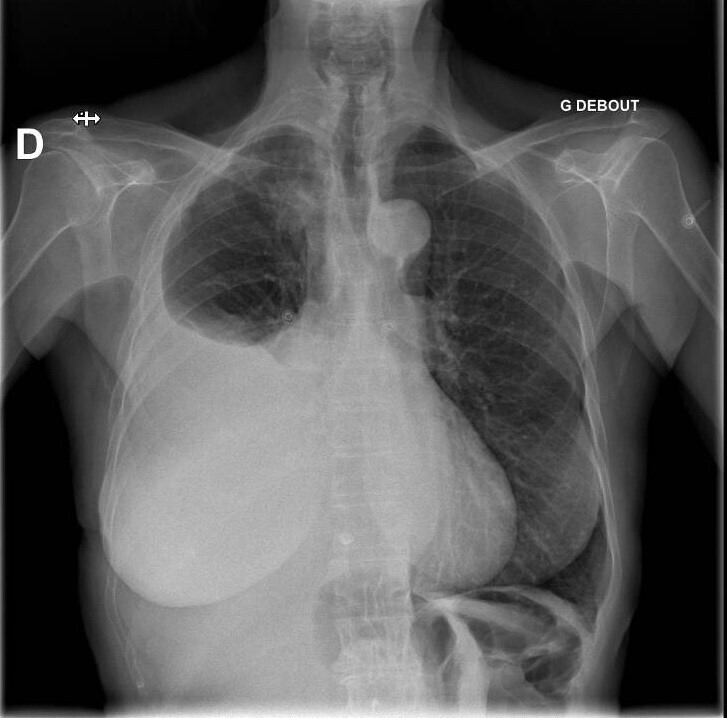

Vous n’observez pas de signe de lutte respiratoire, la dyspnée est silencieuse. L’auscultation pulmonaire retrouve une diminution du murmure vésiculaire à droite, accompagnée de sibilants localisés à mi-hauteur, la percussion révèle une matité. Les bruits du cœur sont réguliers, sans souffle. Il n’y a pas d’œdème des membres inférieurs, les mollets sont souples et indolores. Le reste de l’examen clinique est sans particularité.

Une embolie pulmonaire n’est pas une hypothèse que l’on peut éliminer par la clinique.

Le tableau clinique n’est pas évocateur d’un asthme : les sibilants sont localisés et non diffus, la dyspnée n’est pas bruyante, ni limitée au temps expiratoire. De plus, un asthme aigu grave se définit par un peak flow < 150 L/min ou < 50 % de la théorique, ce qui n’est pas le cas ici. Les sibilants peuvent être le signe d’une obstruction bronchique localisée.